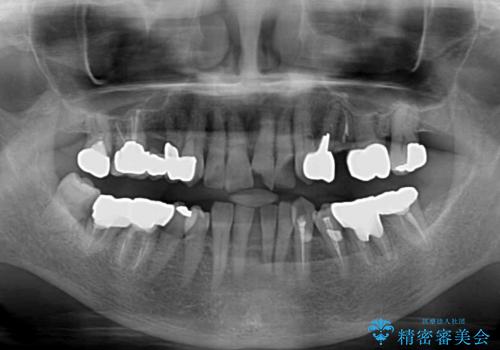

- 長年気にしていた捻れた前歯が欠けたとのことで来院された患者様です。

矯正治療に抵抗があったそうですが、前歯が欠けたことをきっかけに、矯正治療で歯列を整えた上で、セラミッククラウン治療を行う決心が付いたとのことでした。

デコボコが強いため、ブリッジや残根となっている部分のスペースを利用して歯列を整え、変色や欠けている歯をオールセラミッククラウンによる補綴治療を行うこととしました。